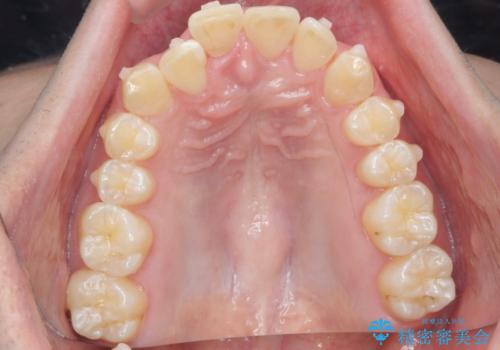

前歯が隠れていて見えない クロスバイトの矯正治療

- 「前歯が1本隠れていて見えない、歯並びを矯正治療で改善したい。」と希望され来院されました。

奥に隠れている前歯を並べられるスペースを確保したのち、歯並びを整えていきます。

前歯のスペース不足により1本だけ後方に位置している状態でしたが、しっかりとスペースを確保し配列することができました。